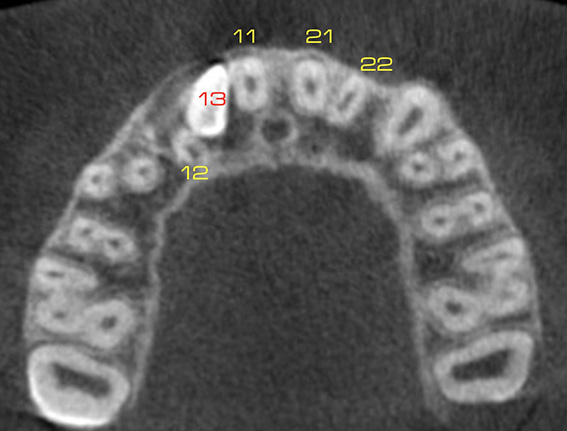

La Tomografia Computerizzata Cone Beam è stata adottata nel nostro studio per l'imaging diagnostico 3D nel 2010.

Non viene utilizzata di routine ma solo in casi complessi seguendo sempre il principio ALARA (As Low As Reasonably Achievable=Esposizione alle radiazioni X il più basso possibile in accordo alle esigenze diagnostiche e terapeutiche).